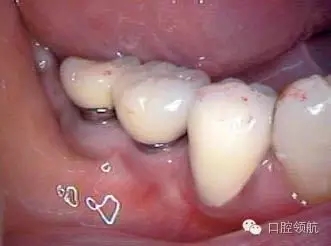

患者, 5 3 歲, 女, 2 0 0 2 年2 月(右下第6、7顆牙) 接受種植治療,采用了一次手術(shù)的方法,SwissPlus種植體(Zimmer公司,直徑3.7mm×長徑10.00mm),6個(gè)月后取印模,制作混合陶瓷上部修復(fù)體(圖1)。

圖1 上部修復(fù)體安裝后的口內(nèi)照片